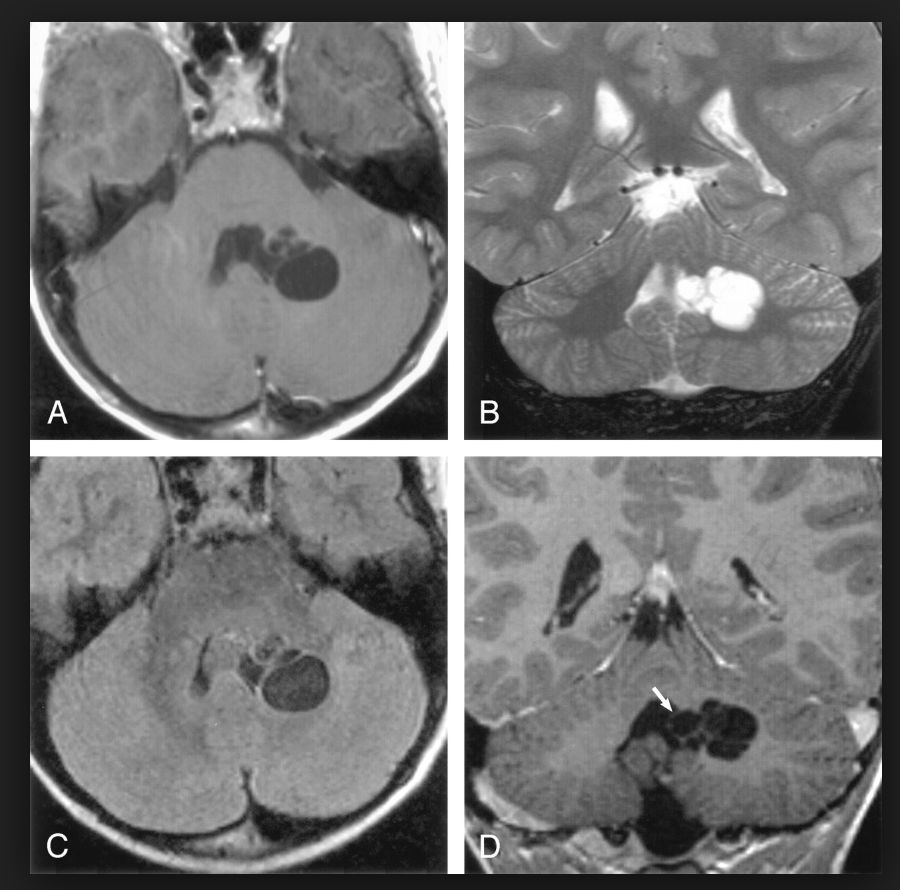

答案揭晓图1 脑内皮样囊肿

图2 脑脓肿

图3 扩大的血管周围间隙

图4 星形胶质细胞瘤

图5 表皮样囊肿